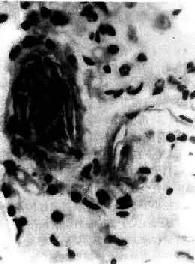

图3-9 肺羊水栓塞

小血管内有角化上皮

羊水栓塞(amniotic fluid embolism)是分娩过程中一种较罕见的疾患。在分娩过程中,如羊膜破裂,尤其又有胎儿头阻塞阴道口时,子宫收缩可将羊水压入破裂的子宫壁静脉窦内,羊水成分可由子宫静脉进入肺循环,在肺动脉分支及毛细血管内引起羊水栓塞。少量羊水可通过肺毛细血管进入大循环引起多数器官小血管的栓塞。镜下,羊水栓塞的证据是在小动脉和毛细血管内发现羊水成分:角化上皮,胎毛,胎脂,胎粪和粘液(图3-9)。本病发病急骤,产妇出现紫绀、呼吸困难和休克,绝大多数导致死亡。羊水成分栓塞肺血管所致的肺循环机械性阻塞,实不足以解释上述症状,因此过敏性休克、DIC、羊水液体内所含的血管活性物质进入血液引起血管反应可能是致死的原因。羊水具有凝血致活酶作用,可引起DIC,一些羊水栓塞病例,肺微血管内有纤维素性血栓存在。